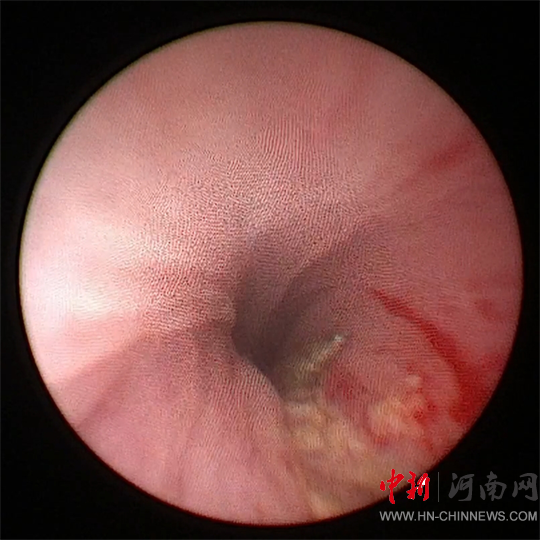

為了盡量減少對(duì)尿道的創(chuàng)傷

團(tuán)隊(duì)決定嘗試

經(jīng)尿道應(yīng)用

小兒輸尿管鏡微創(chuàng)手術(shù)

將鋼針取出

然而,手術(shù)面臨

患兒尿道較細(xì)

鋼針堅(jiān)硬且長(zhǎng)

刺入尿道組織較深等問題

徐海亮團(tuán)隊(duì)經(jīng)過

充分術(shù)前準(zhǔn)備

采用小兒輸尿管鏡

和異物鉗進(jìn)行手術(shù)

因鋼針嵌頓于尿道壁

并伴局部組織炎癥水腫

徐海亮在精細(xì)操作下

謹(jǐn)慎調(diào)整異物角度

一點(diǎn)一點(diǎn)往外取

歷時(shí)20分鐘

順利將鋼針取出